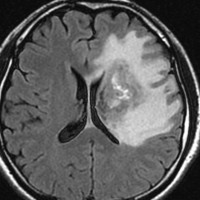

アバスチン投与後15日目

たった2週間で劇的な改善が見られました。失語症と片麻痺や認知機能も改善しました。

4回目のアバスチン投与後

アバスチンをどれだけ続ければいいのかははっきりしていません。2週間おきに6コースまでの投与が基本かもしれません。

この画像を見ると,放射線とテモダールの治療が有効であったのかなと思います。